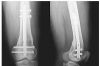

24/05/2015 | El Dr Nicolas Gonzalez Masanes, integrante de la Unidad de Patologia Espinal (UPE), presento el trabajo "Hangman's fracture: treatment with fluoroscopically guided transcutaneos pedicle screws/ Tratamiento percutaneo de la fractura de Hangman con tornillos guiados por fluoroscopia".